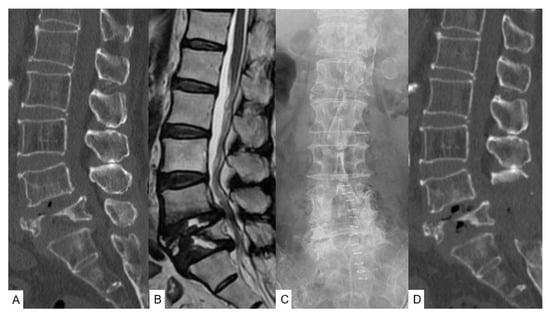

2.3. Preoperative Imaging

2.4. First Surgery and Postoperative Images

2.5. Second Surgery and Postoperative Images